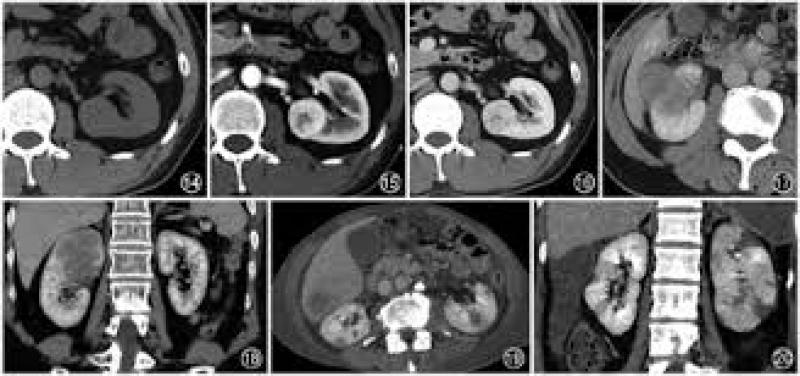

目前,北京清华长庚医院核医学科可开展18FDG-PET/CT全身显像、18FDG-PET/CT脑代谢显像、18FDG-PET/CT心肌代谢断层显像,临床主要应用于肿瘤、脑和心脏等疾病的早期发现和诊断。除此之外,SPECT/CT和PET/CT的应用,可对钇90治疗患者进行治疗前评估、钇90剂量计算和治疗后的疗效评价。